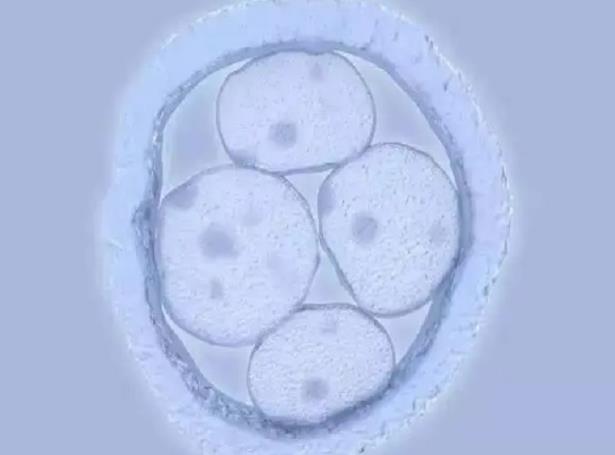

山西省三代试管生男孩医院排名一览,附最新试管费用清单!目前,山西省有12家医院被国家主管部门批准开展辅助生殖技术,其中11家医院可以同时开展第一代和第二代试管婴儿助孕技术,只有1家医院可以开展第三代试管婴儿助孕技术。因为很多家庭看到第三代试管婴儿技术可以筛选出胎儿的性别,所以想通过这种技术实现生男孩的愿望。

以上11家医院都是山西省内可以做试管婴儿的医院,其中只有一家医院可以做第三代试管婴儿,就是山西省妇幼保健院,但是没有试管婴儿男孩的服务。只有在符合相关医学证明的情况下才允许。因为中国明确规定不允许通过试管婴儿技术进行性别选择,第三代试管婴儿的最初目的是筛选出有遗传缺陷和遗传病的胚胎,帮助准父母获得没有遗传病的健康婴儿。